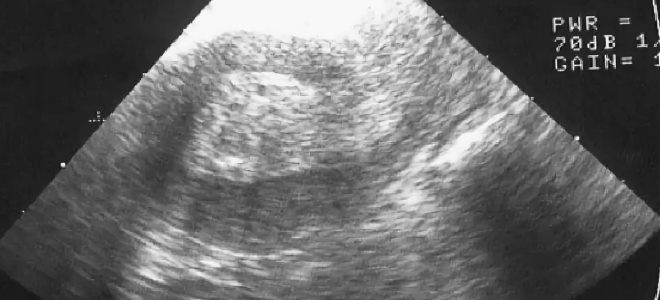

Гипоплазия эндометрия, или его истончение, не проявляется ярко выраженными и специфическими симптомами. Признаки тонкого эндометрия часто могут быть скрыты под другими гинекологическими заболеваниями и расстройствами. Определить наличие данной патологии возможно только с помощью ультразвукового исследования. Диагноз гипоплазия устанавливается, если толщина эндометрия составляет менее 8 мм.

Регулярные визиты к гинекологу и прохождение необходимых обследований помогут выявить возможные проблемы на ранних стадиях. Ультразвуковое исследование может помочь контролировать толщину эндометрия и выявить любые отклонения. При наличии хронических заболеваний, таких как поликистоз яичников или эндометриоз, важно следовать рекомендациям врача и проходить лечение.